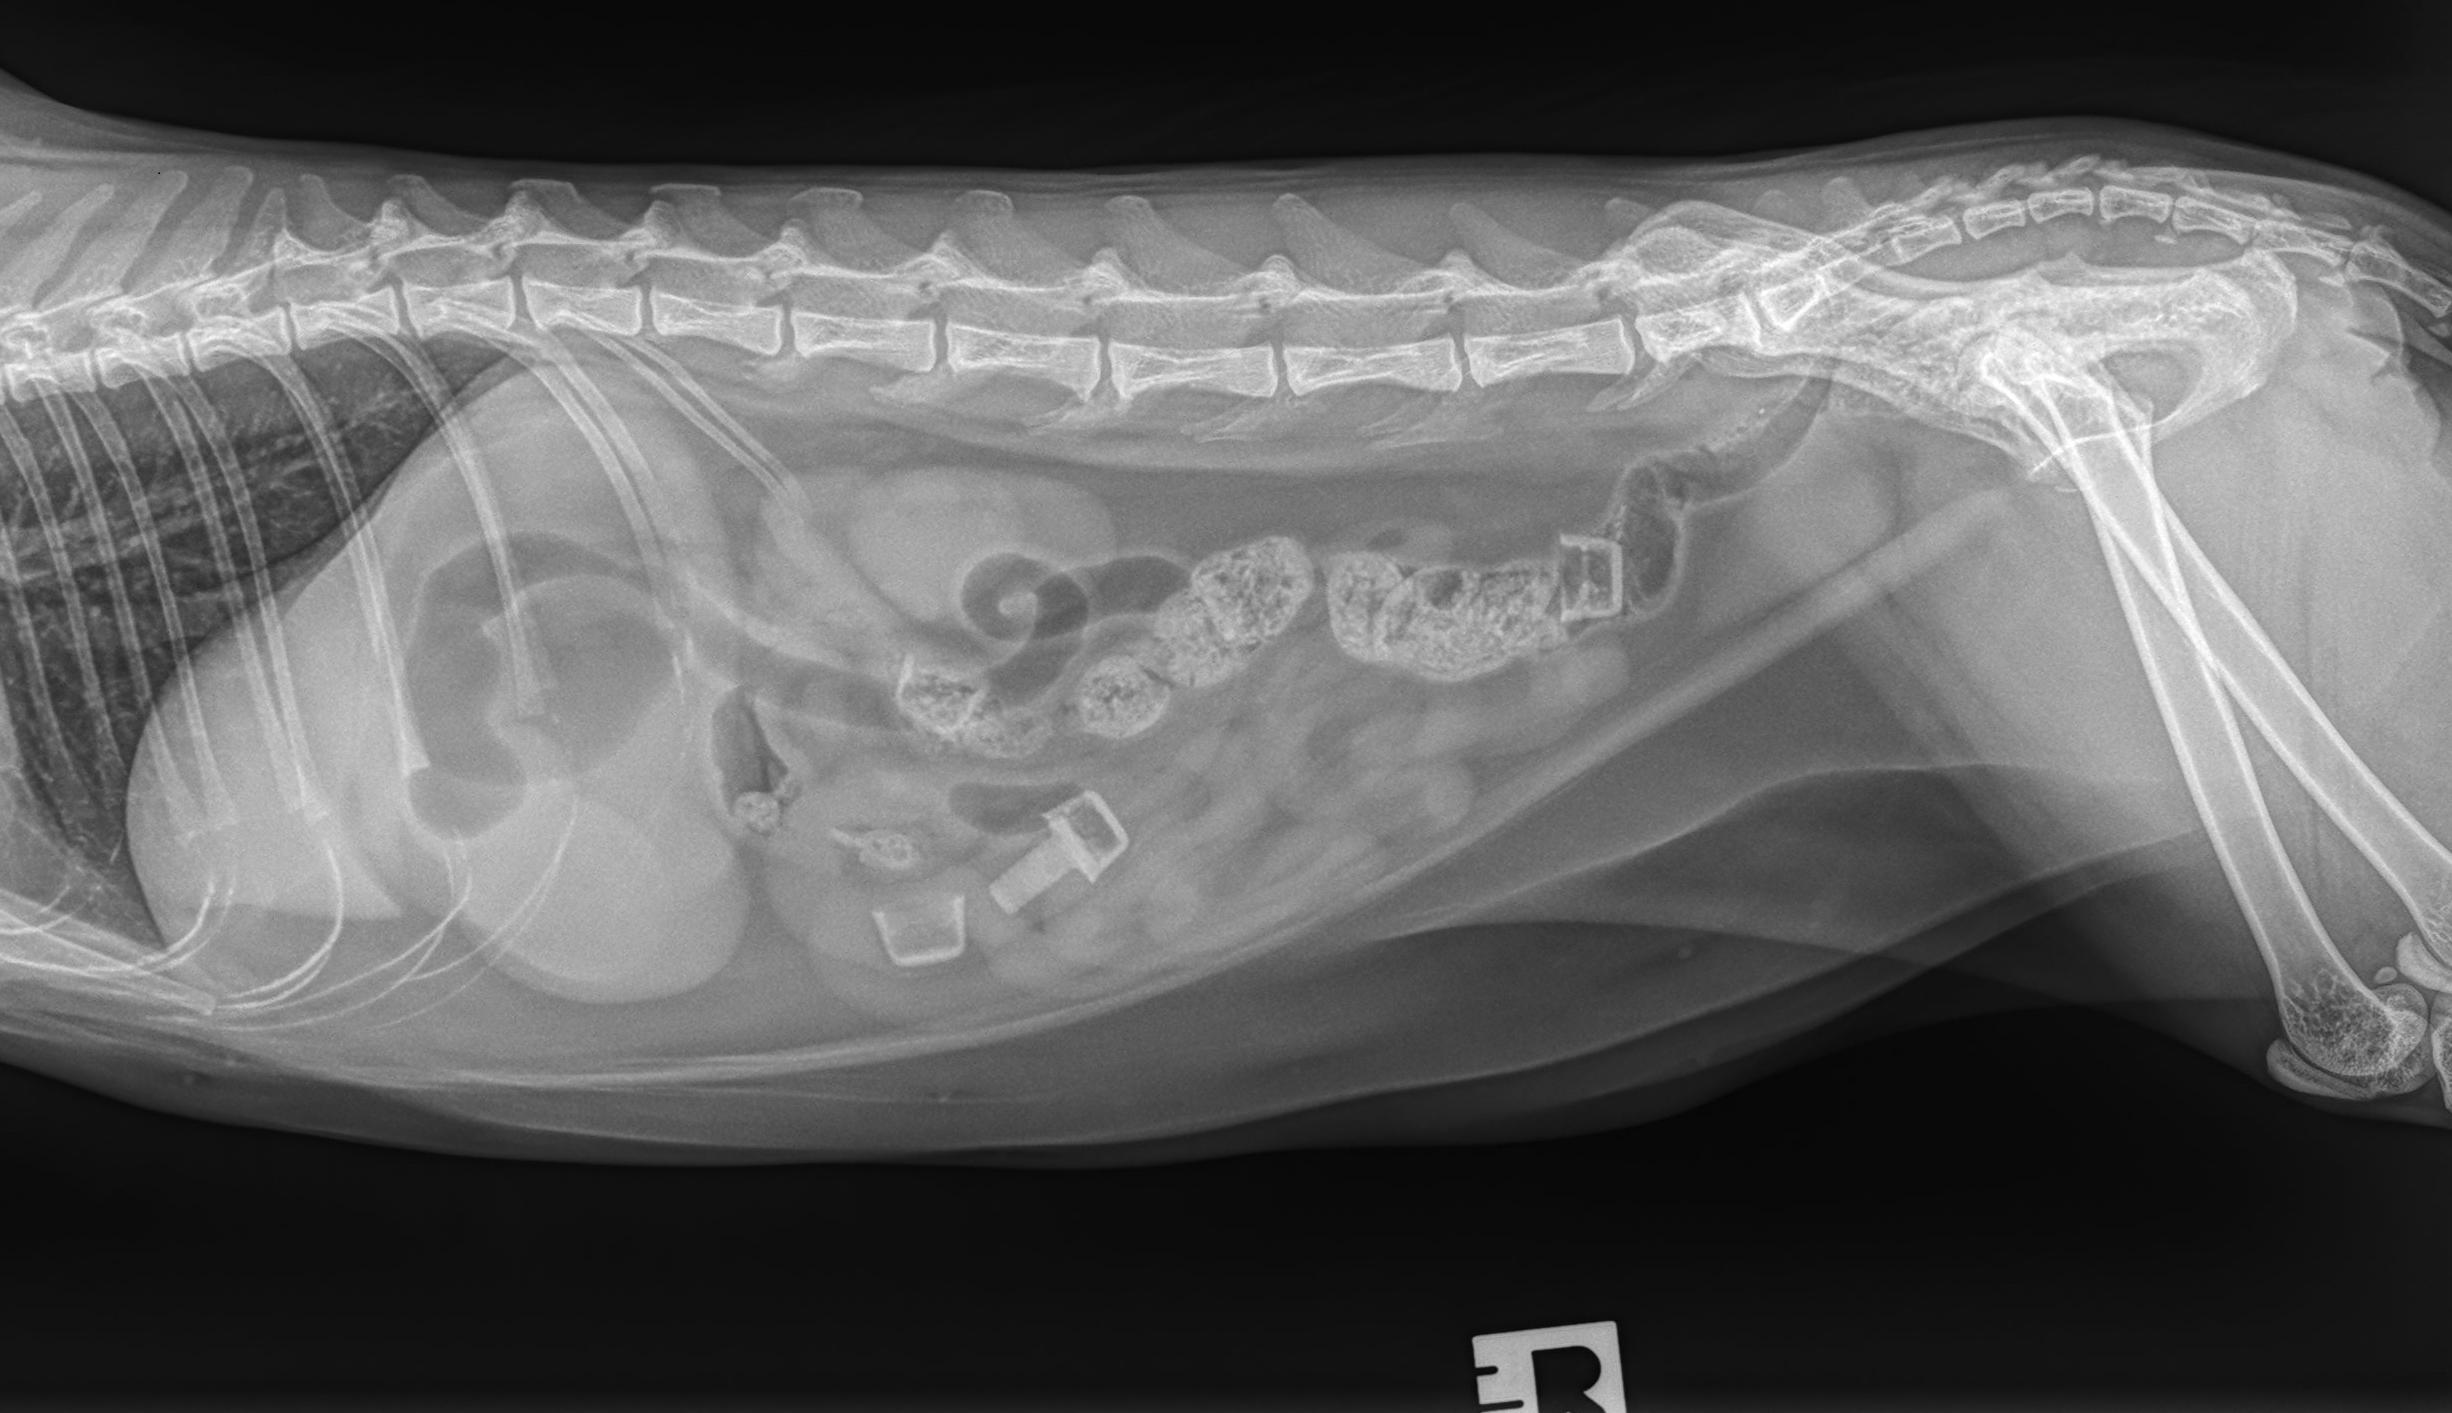

Beschrijving van de röntgenfoto's

Het serosale detail is binnen de normale grenzen. Er bevinden zich vier Nerf-kogels in het maagdarmkanaal: twee in het colon en twee in de dunne darm. Enkel het rubberachtige deel van de kogels is aanwezig en slechts één is volledig, van de overige is enkel het uiteinde zichtbaar. Er is een matige dilatatie van de maag met gas en vocht. De dunne darm is voornamelijk met vocht gevuld, met lichte gasdilatatie. De rest van het abdomen vertoont geen afwijkingen.

- Nerfgun-kogels in het maagdarmkanaal: Twee in de dikke darm, twee in de dunne darm.

- Opletten voor een mechanische obstructie, vanwege dilatatie van de maag en de dunne darm (minstens van partiële aard). De aanwezigheid van twee kogels in het colon kan echter wijzen op mogelijke spontane passage. Herhaalde abdominale radiografie en of abdominale echografie kan overwogen worden binnen 8 tot 12 uur, of eerder indien de patiënt klinisch verslechtert of niet verbetert, voor verdere evaluatie indien klinisch geïndiceerd. Als alternatief kan een chirurgische exploratie overwogen worden indien klinisch geïndiceerd.